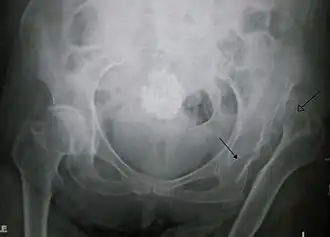

| Deslocação congénita da anca esquerda numa pessoa idosa. A seta fechada indica o acetábulo, a seta aberta a cabeça do fémur | |